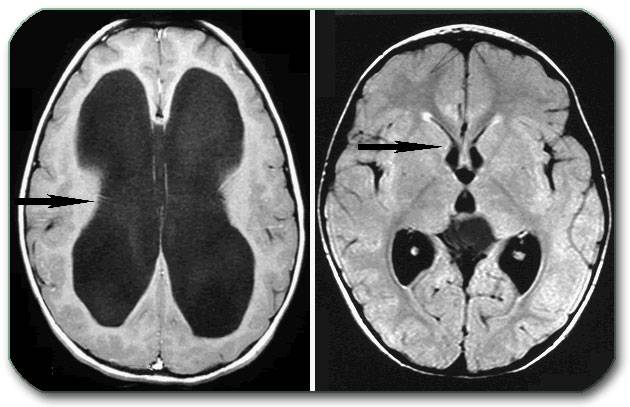

МРТ визуализирует жидкость, присутствующую в мозговых структурах, определяет степень тяжести заболевания, его форму. Данный метод позволяет назвать предположительную причину формирования водянки. КТ дополнительно подтверждает информацию, полученную в ходе проведения магнитно-резонансной томографии.

- КТ или МРТ. Вторая процедура считается более безопасной.

В сутки цереброспинальная жидкость обновляется 4 раза и достигает количества в мозгу до 700 мл. При водянке это число увеличивается. Ликвор начинает скапливаться в желудочковой системе, затрудняется его перемещение к головному и спинному мозгу, развивается тяжелый гипертензионно-гидроцефальный синдром. У человека повышается давление внутри черепа, наблюдаются неврологические и расстройства органов чувств.

МРТ головного мозга. Точное сканирование с возможностью получения трехмерного изображения сосудов, структурных изменений посттравматического характера, изучения коркового и мозгового вещества, гипофиза. Часто предупреждает кровоизлияние и наступление ишемического инсульта.

Компьютерная томография, КТ головного мозга. Лучевая методика обследования, которая дает возможность обнаружить не только аномалии костных структур, но и изменения мягких тканей, воспалительные процессы мозговых оболочек.